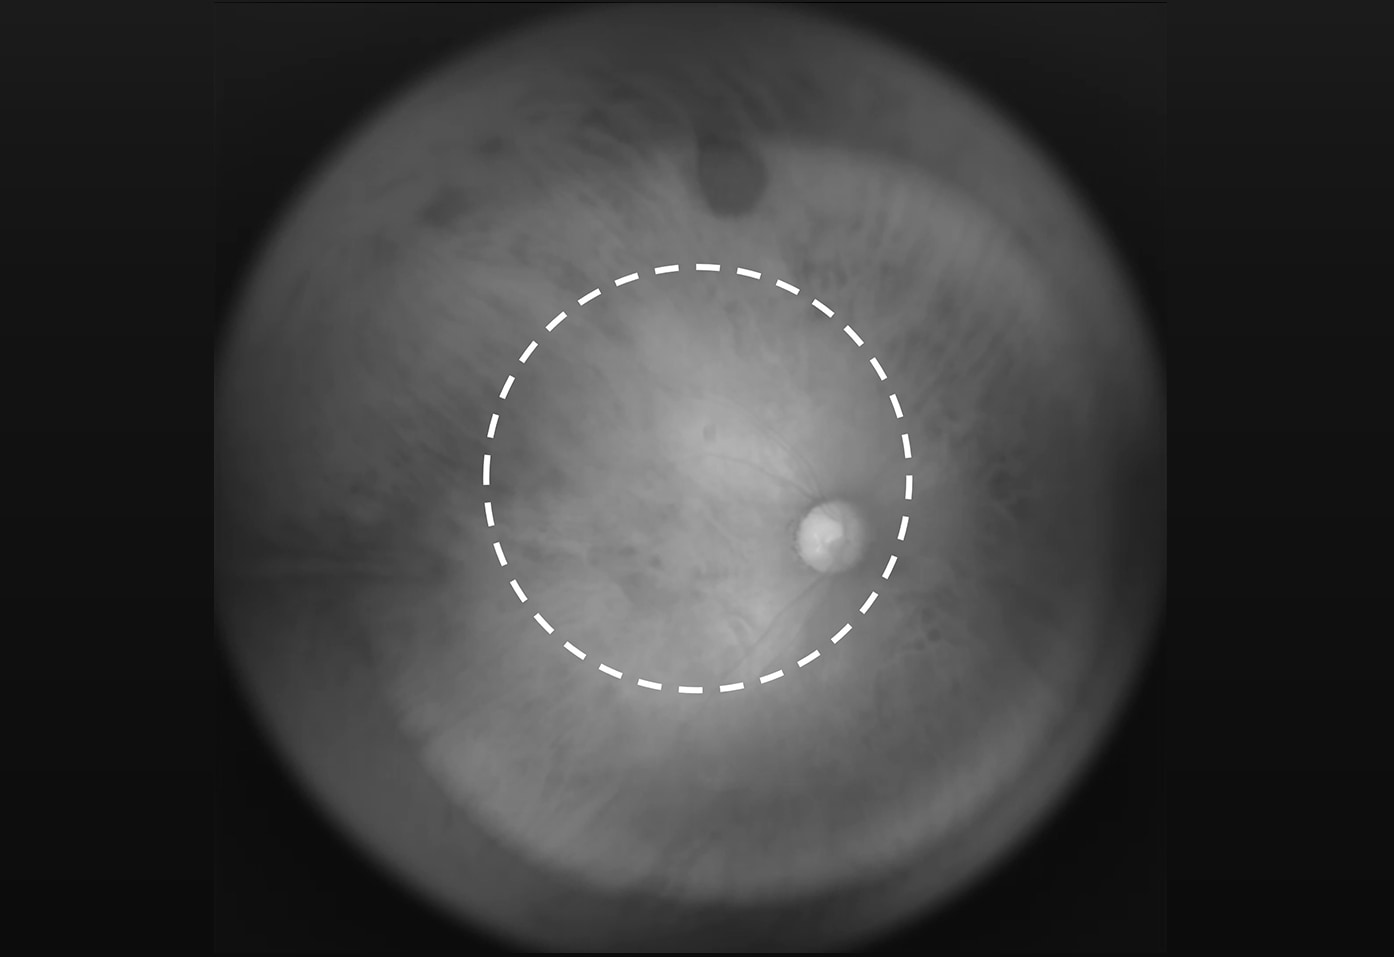

• 日本人の主な失明原因となる緑内障、網膜色素変性症、糖尿病網膜症を早期に発見するために用いられるのが眼底カメラです。より広い視野角で眼底を撮影し検査できることが求められますが、現在、健康診断で用いられている普及型の眼底カメラは視野角が60度程度であり、眼底の一部しか検査できません。眼底という凹面の球体をクリアに撮影するためのレンズ設計、眼底へレンズを通して光を投射する難しさがあります。

タムロンでは、眼底撮影に適した超広角のレンズを専用設計・試作。奈良先端科学技術大学院大学で開発された近赤外光を利用した眼底カメラに組み込み、視野角約180度の超広角眼底撮影に成功しました。瞳孔を拡げるための散瞳剤(点眼薬)を使用することなく、広範囲の眼底像の取得が可能になります。